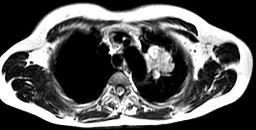

问题 男,68岁,声音嘶哑半个月,行MRI检查如图,其最可能的诊断为 ( )

选项 A.右上肺癌 B.左上肺结核球 C.左上肺炎性假瘤 D.左上肺癌 E.左上肺动静脉瘤

答案 D